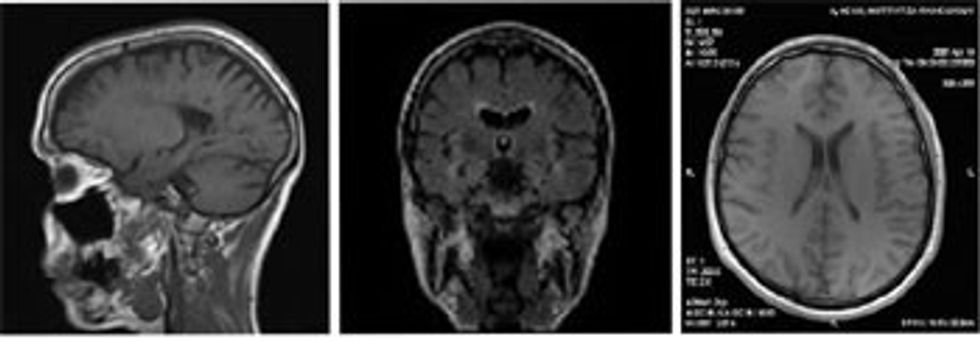

Zakonisht IRM realizohet përmes përdorimit të së paku dy e më shumë sekuencave në rrafshe të ndryshme dhe secila zgjatë nga 50 sekonda deri pesëmbëdhjetë minuta. Secila sekuencë përfiton shkallë të caktuar të kontrastit mes parenkimës së imazhuar dhe mund të punohet në rrafshe të ndryshme (nga djathtas kah majtas – sagjitale, nga përpara në drejtim prapa – frontale, nga lartë poshtë – transverzale).

• Imazhet e fituara të trurit dhe strukturave tjera të kokës me RM janë më të qarta se me metodat tjera imazhuese.

• IRM mundëson detektimin e abnormaliteteve, vizualizimi i të cilave nuk është i mundur me metodat tjera imazhuese, për shkak të pranisë së kockave të kokës të cilat krijojnë artefakte.